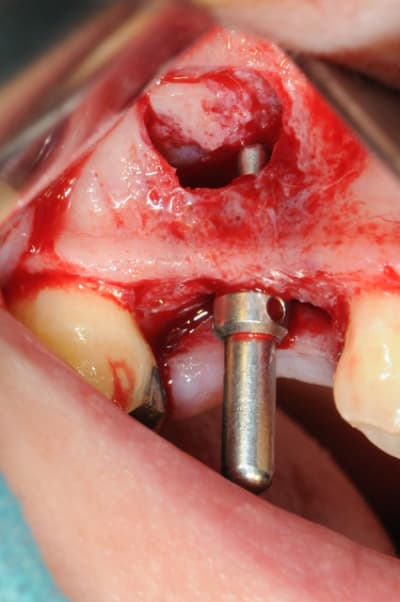

- mise en place de l'implant

- séchage discret de la surface osseuse

- injection du Vital Os en palatin et partout autour de l'implant

- hé hé hé ... pas de membrane de recouvrement, le matériaux se suffit à lui même. d'où une petite économie substantielle pour ceux qui ont l'habitude de mettre systématiquement une membrane après un Caldwell-Luc.

- sutures...